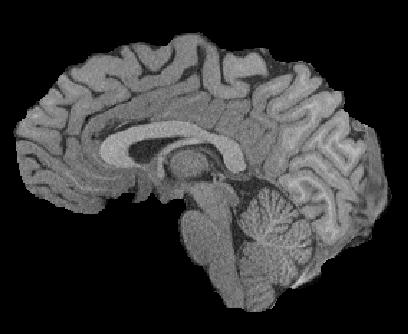

Magnetic resonance (MR) images are often acquired in 2D settings for real clinical applications. The 3D volumes reconstructed by stacking multiple 2D slices have large inter-slice spacing, resulting in lower inter-slice resolution than intra-slice resolution. Super-resolution is a powerful tool to reduce the inter-slice spacing of 3D images to facilitate subsequent visualization and computation tasks. However, most existing works train the super-resolution network at a fixed ratio, which is inconvenient in clinical scenes due to the heterogeneous parameters in MR scanning. In this paper, we propose a single super-resolution network to reduce the inter-slice spacing of MR images at an arbitrarily adjustable ratio. Specifically, we view the input image as a continuous implicit function of coordinates. The intermediate slices of different spacing ratios could be constructed according to the implicit representation up-sampled in the continuous domain. We particularly propose a novel local-aware spatial attention mechanism and long-range residual learning to boost the quality of the output image. The experimental results demonstrate the superiority of our proposed method, even compared to the models trained at a fixed ratio.